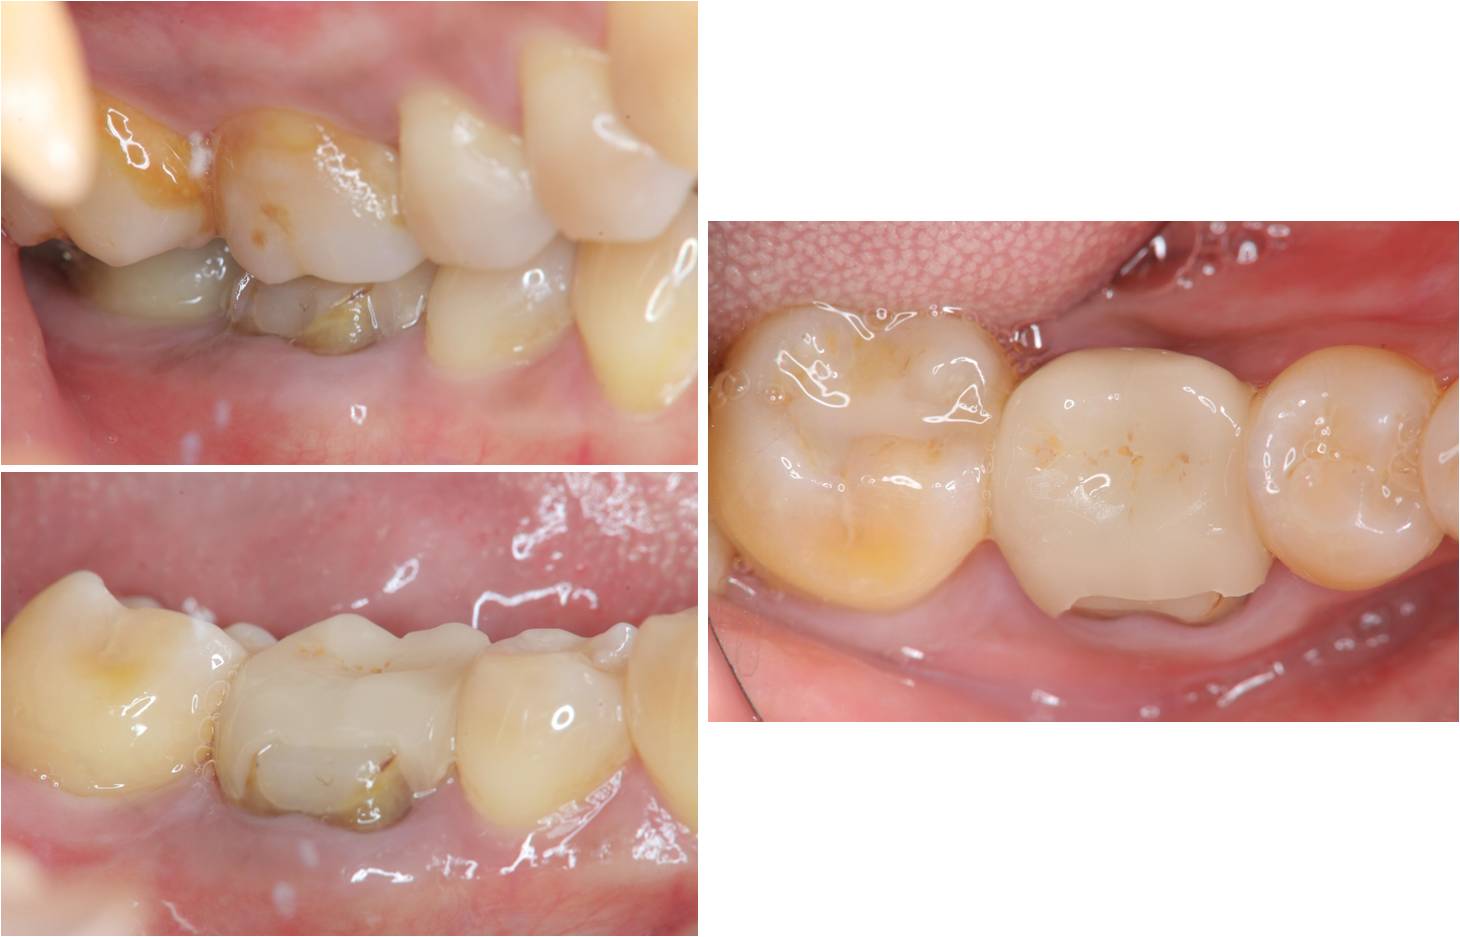

治療前,假牙崩壞

治療前,根管治療後組織良好